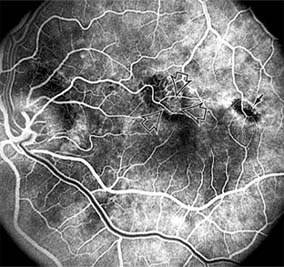

1. NONPROLIFERATIVE DIABETIC RETINOPATHY

Diabetic retinopathy is a progressive microangiopathy characterized by small vessel damage and occlusion. The earliest pathologic changes are thickening of the capillary endothelial basement membrane and reduction of the number of pericytes. Background diabetic retinopathy is a clinical reflection of the hyperpermeability and incompetence of involved vessels. The capillaries develop tiny dot-like outpouchings called microaneurysms, while the retinal veins become dilated and tortuous (Figure 10-20).

Figure 10-20

Figure 10-20: Background diabetic retinopathy with abundant macular exudate (open arrow), micro-aneurysms (small arrow), and intraretinal hemorrhage (large arrow).

Multiple hemorrhages may appear throughout different levels of the retina. Flame-shaped hemorrhages are so shaped because of their location within the horizontally oriented nerve fiber layer, while dot and blot hemorrhages are in the deeper retina, where cells and axons are vertically oriented.

Macular edema is the most frequent cause of visual loss among patients with background diabetic retinopathy. The edema is caused primarily by a breakdown of the inner blood-retinal barrier at the level of the retinal capillary endothelium, allowing leakage of fluid and plasma constituents into the surrounding retina. The edema may be focal or diffuse and appears clinically as thickened, cloudy retina with associated microaneurysms and intraretinal exudate. Circinate zones of yellow, lipid-rich exudate may form around clusters of microaneurysms and are most frequently centered in the temporal portion of the macula. While the prevalence of macular edema is 10% in the diabetic population as a whole, there is a dramatic increase in prevalence in eyes with more severe retinopathy.

With progressive microvascular occlusion, signs of increasing ischemia may be superimposed on the picture of background retinopathy and produce the clinical picture of preproliferative diabetic retinopathy. The most typical findings here are multiple cotton-wool spots, beading of the retinal veins, and irregular segmental dilation of the retinal capillary bed (intraretinal microvascular abnormalities). Closure of retinal capillaries surrounding the foveal avascular zone may cause significant ischemia, manifest clinically by the presence of large dark retinal hemorrhages and small thread-like macular arterioles. Eyes with macular edema and significant ischemia have a poorer visual prognosis-with or without laser treatment-than eyes with edema and relatively good perfusion.

The visual and electrophysiologic dysfunctions associated with diabetes probably result from the local vascular abnormalities and the systemic metabolic effects of the disease to which the retina is subjected. A characteristic blue-yellow color vision abnormality develops, and hue discrimination may be impaired. Contrast sensitivity may be reduced in patients, even in the presence of normal visual acuity. Visual field testing may show relative scotomas corresponding to areas of retinal edema and nonperfusion, and abnormalities in dark adaptation have also been described. Electroretinographic abnormalities bear a relationship to the severity of retinopathy and may aid in predicting progression of retinopathy. Fluorescein angiography is invaluable in defining the microvascular abnormalities of diabetic retinopathy (Figures 10-21 and 10-22). Large filling defects of capillary beds-"capillary nonperfusion"-show the extent of retinal ischemia (Figure 10-23) and are usually most prominent in the midperiphery. The fluorescein leakage associated with retinal edema may assume the petaloid configuration of cystoid macular edema or may be diffuse. Other fluorescein abnormalities include vascular loops and intraretinal shunts. The focus of treatment in patients with nonproliferative diabetic retinopathy and no macular edema is treatment of hyperglycemia and intercurrent systemic disease. A controlled clinical trial has shown that aldose reductase inhibitor therapy does not prevent progression of diabetic retinopathy. Focal argon laser treatment of discrete points of retinal leakage in patients with clinically significant macular edema, principally defined as thickening of the retina at or within 500 0x0003bcm of the center of the macula, reduces the risk of visual loss and increases the likelihood of visual improvement (see Chapter 24). Eyes with diabetic macular edema that is not clinically significant should usually be monitored closely without laser treatment. Since macular edema may be present with little or no change in visual acuity and requires slitlamp biomicroscopic retinal examination for full evaluation, primary health care providers should recognize the importance of prompt and early referral of diabetic patients to the ophthalmologist.

Figure 10-21

Figure 10-21: Fluorescein angiogram in nonproliferative diabetic retinopathy shows microaneurysms (arrow) and perifoveal retinal vascular changes.

Figure 10-22

Figure 10-22: Late phase fluorescein angiogram shows hyperfluorescence typical of noncystoid diabetic macular edema.

Figure 10-23

Figure 10-23: Fluorescein angiogram shows hypofluorescence from capillary drop-out (arrows) typical of ischemic diabetic maculopathy.